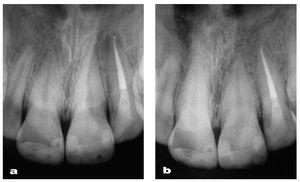

El pulido final es fundamental para el éxito estético de las restauraciones, ya que una superficie brillante y lisa reduce el acúmulo de placa y previene la decoloración de los dientes (Shiny System, Micerium). Al final, la restauración pulida presentaba una superficie muy similar a la del diente natural (figuras 49 y 50). No obstante, este nivel de resultado clínico obtenido con una técnica directa sólo es posible con un manejo correcto de la forma y la reconstrucción. Estos parámetros deben ser determinados antes de instaurar los procedimientos clínicos (figuras 51 y 52).

Figura 51 Control radiográfico de las restauraciones y la endodoncia (a) y control radiográfico de las restauraciones dos años después del tratamiento (b) con resolución de la imagen periapical translúcida.

Figura 52 Revisión a los dos años.